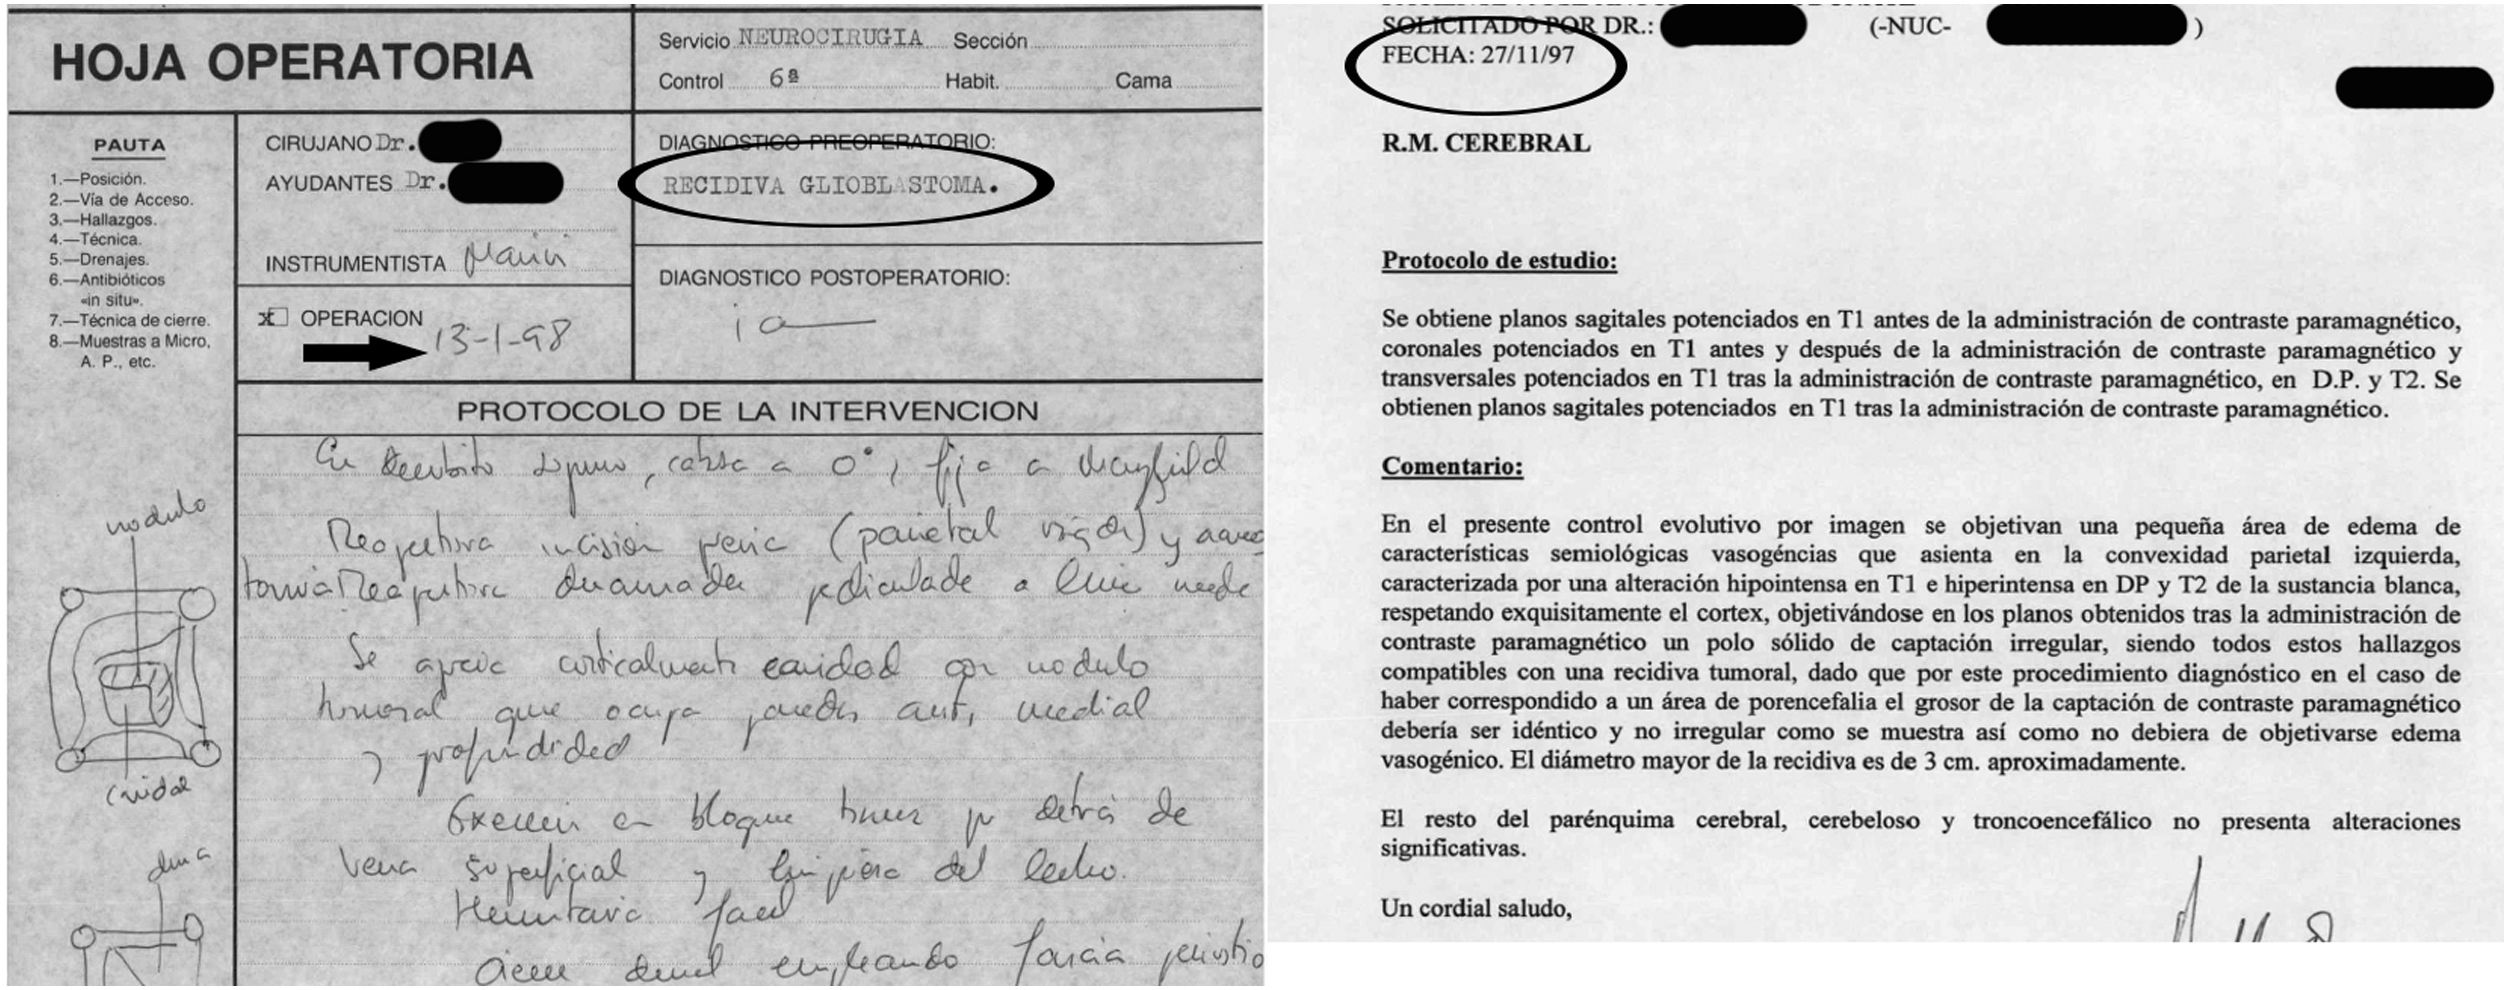

Material and methodWe realize a systematic analysis and identify important factors for long survivor patients. We also show an own case with more of 20 years of survival. We make a new pathological study of the old paraffin block of this patient.

ResultsThe most important variable associated with long-survival between all multivariant studies is the age. When we try to find genetic and molecular alterations in glioblastoma associated with prolongated survival, the MGMT promoter methylation play the most important role. We find a correct diagnosis in the current analysis of our patient’s sample with very long survival.

Material y métodosSe realiza un análisis sistemático de la literatura identificando los factores que pueden influir en los pacientes de larga supervivencia. Se identifica un caso en nuestro medio de más de 20 años de supervivencia realizándose un análisis actual del bloque de parafina que se conservaba del paciente.

ResultadosLa variable que más se asocia a la larga supervivencia en todos los análisis multivariantes es la edad, aunque, cuando se analiza las características genéticas y moleculares de los tumores, parecen existir otras variables como la metilación del promotor MGMT que juegan un papel muy importante. El análisis anatomo-patológico actual de la muestra comprueba la certeza del diagnóstico en nuestro paciente de muy larga supervivencia.